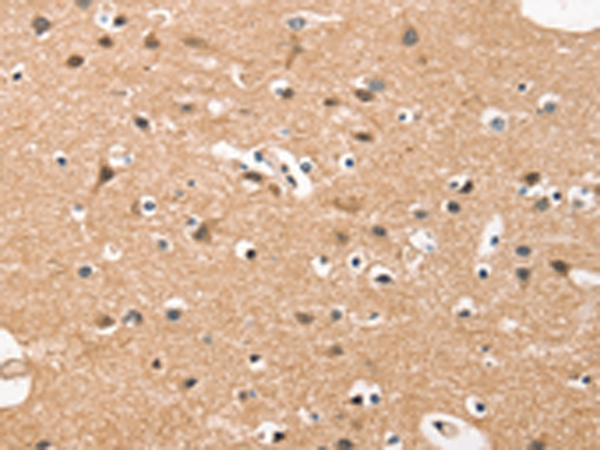

IHC positive control: |

Human brain and human esophagus cancer |